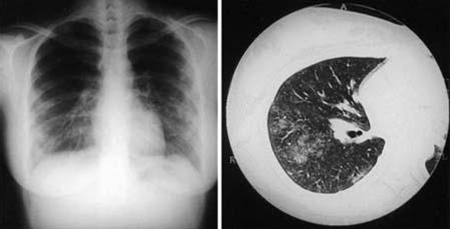

გულმკერდის რენტგენოლოგიური კვლევით

შეიძლება საჭირო გახდეს როგორც მწვავე, ასევე პერსისტენტული ფოკალური დაავადების შემთხვევაში, ფილტვის გართულებებზე ეჭვის დროს.

დასკვნები შეიძლება მერყეობდეს ორივე ფილტვის ნორმალურიდან მრავლობით არასპეციფიკურ( დამახასიათებელი სურათის ან გავრცელების გარეშე)გამჭვირვალობამდე, რაც ყველაზე მეტად შეესაბამება ატიპიურ პნევმონიას. გულმკერდის რადიოგრაფიაზე ყველაზე ხშირი პათოლოგიებია სეგმენტური ან წილოვანი დაჩრდილვები. Q ცხელების პნევმონიის დამახასიათებელი ნიშანია რამდენიმე მრგვალი დაჩრდილვა, თუმცა ეს იშვიათია.[38]

შეიძლება გამოვლინდეს პლევრული გამონაჟონი, ატელექტაზი, ჰილარული ლიმფადენოპათია, თუმცა იშვიათია.

პერსისტენტული ფოკალური ინფექციის მქონე პაციენტებში გულმკერდის რენტგენზე შეიძლება გამოვლინდეს ორი განსხვავებული პერსისტენტული ინფექცია: ინტერსტიციული ფიბროზის და ფილტვის ფსევდოსიმსივნე.[Figure caption and citation for the preceding image starts]: Coxiella burnetii-ით გამოწვეული პნევმონია გულმკერდის რენტგენი და CT სკანირება- 21 წლის ქალი Coxiella burnetii პნევმონიით; რენტგენზე ჩანს რბილი კონსოლიდაციის მრავლობითი წერტილი ორმხრივად, ქვედა-შუა წილებში; CT -ზე ჩანს ცუდად გამოკვეთილი ცენტრალური კვანძები და ჰაერის სივრცის კონსოლიდაციაOkimoto N, et al. Respirology. 2004;9:278-282; used with permission of John Wiley & Sons Ltd [Citation ends].

როგორც წესი, ეს კვლევები რუტინულად არ არის საჭირო, თუმცა შეიძლება გამოიყენოთ ფილტვის გართულებების შესაფასებლად მწვავე ინფექციის დროს.[Figure caption and citation for the preceding image starts]: Coxiella burnetii-ით გამოწვეული პნევმონია გულმკერდის რენტგენი და CT სკანირება- 21 წლის ქალი Coxiella burnetii პნევმონიით; რენტგენზე ჩანს რბილი კონსოლიდაციის მრავლობითი წერტილი ორმხრივად, ქვედა-შუა წილებში; CT -ზე ჩანს ცუდად გამოკვეთილი ცენტრალური კვანძები და ჰაერის სივრცის კონსოლიდაციაOkimoto N, et al. Respirology. 2004;9:278-282; used with permission of John Wiley & Sons Ltd [Citation ends].